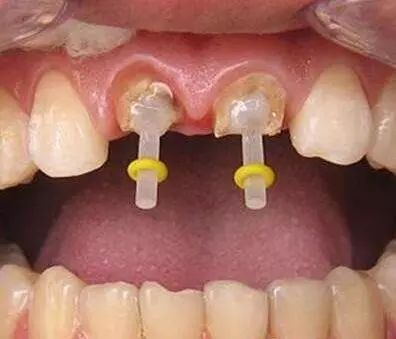

一些人在进行根管治疗后,会进行牙齿打桩。牙齿打桩是指在患者牙齿缺损较大,或因为外伤等原因只剩下牙根时,因剩下的牙齿过短或力量过于薄弱,不能用修复体直接修复,需要给牙根里打桩,加固并延长折断的牙齿,以使假牙能获得足够的力量固定。下面口腔专家给大家具体介绍一下牙齿打桩的相关知识。

什么是牙齿打桩?

牙齿打桩是指插入根管内的部分,利用摩擦力和粘固力、粘接力获得固位,进而为最终修复体提供固位。